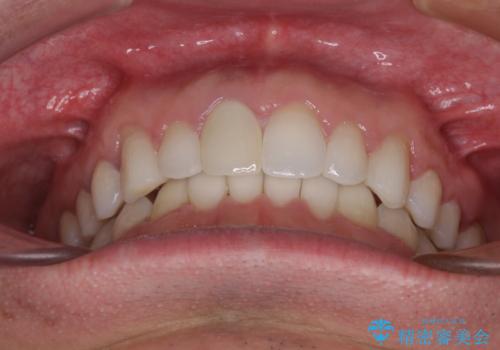

口が閉じにくい インビザラインによる矯正治療

- 口の閉じにくさを気にして来院された患者様です。

患者様と相談の上、横顔の印象から抜歯矯正は必要ないと判断し、IPR(歯と歯の間)並びに歯列全体の後方移動により口元の突出感の改善することとしました。

しっかりと装着時間を守り、ゴムかけも徹底していただいたので、思いの外口元を引っ込めることができました。

これ以上の改善を望まれましたが、非抜歯矯正でこれ以上口元を引っ込めると食いしばりすやすい咬合となるため、この歯列で終了としました。